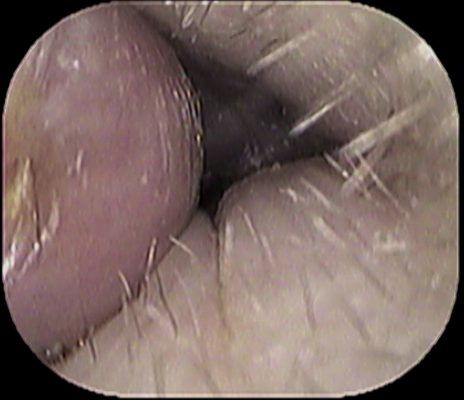

岩倉市の「いのうえ耳鼻咽喉科」 院長の井上です。

先日の「耳掃除 その①」のブログの続きです。

「耳掃除のし過ぎ→外耳炎になってしまう」とお伝えしたのですが、

それが年単位で長期間に及ぶと↓

このように、骨隆起(骨として出っ張ってしまうこと)となっておられる方がおられます。

耳搔きを使う方や(綿棒でも)毎日耳掃除している方は、要注意です

耳垢の性状・溜まる状況は、個人差によるところが大きいのですが、

「耳掃除をほとんどしない」「1~2週間に1度くらいの掃除」がベストです。